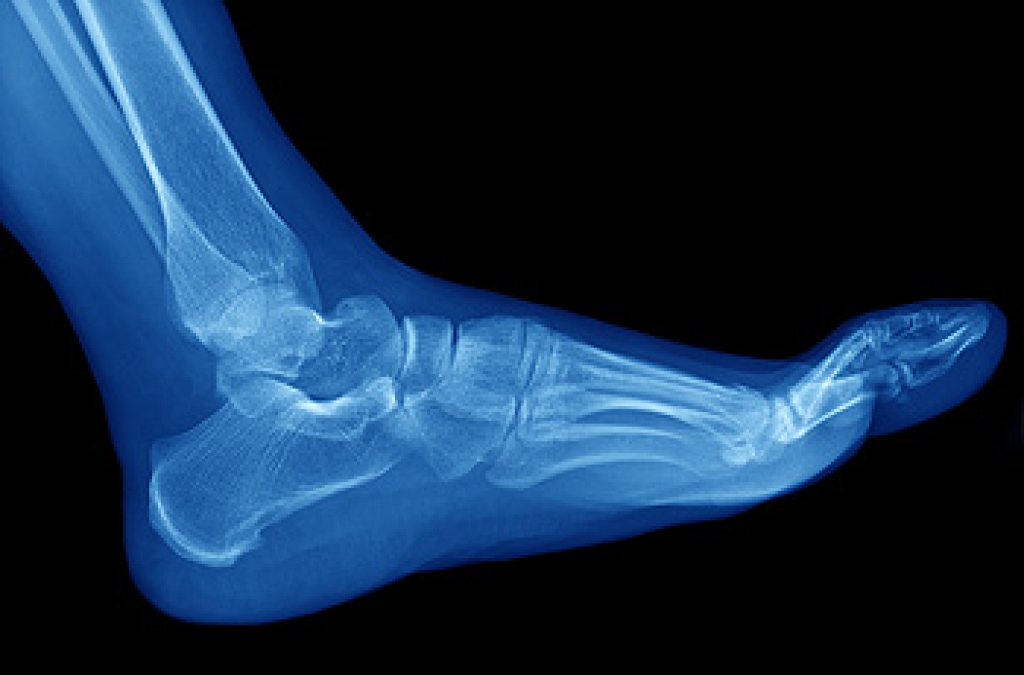

Ankle pain is any condition that causes pain in the ankle. Due to the fact that the ankle consists of tendons, muscles, bones, and ligaments, ankle pain can come from a number of different conditions.

Due to the wide variety of potential causes of ankle pain, podiatrists will utilize a number of different methods to properly diagnose ankle pain. This can include asking for personal and family medical histories and of any recent injuries. Further diagnosis may include sensation tests, a physical examination, and potentially x-rays or other imaging tests.